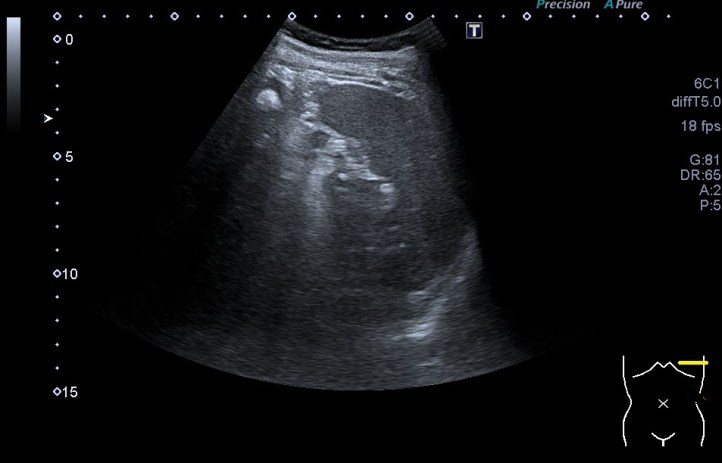

Lo primero normalidad:

En la inserción en el Calcáneo por la parte posterior las líneas amarillas marcan los diferentes grosores normales que adopta el tendón(hiperecogénico), desde su inserción distal hasta donde se hace más grande en el tercio distal de la pierna.

La flecha rosa marca una ligera cantidad de líquido normal que encontraremos justo encima de la línea hiperecogénica bajo el tendón y que corresponde con el calcáneo.

Cuanto más proximal es el tendón, más se aleja de la inserción, más fino se hace…

En las siguiente imágenes vemos normalidad de fibras y grosores, con grosores y alteración del patrón normal del tendón…

La imagen superior muestra un corte longitudinal del tendón tendinopático con técnica panorámica desde la inserción hasta el tercio medial de la pierna por la parte posterior, lógicamente.